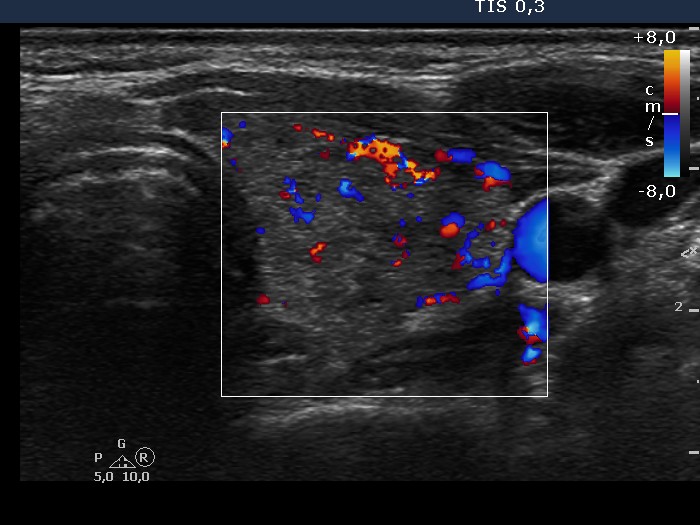

Graves' disease - Case 25. (ultrasonographic picture 6)

Left lobe, horizontal scan, color Doppler mode. The vascularization is a little bit increased.